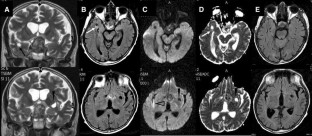

Fig. 2

Patient 1 was a 76-year-old woman with right hemiparesis and aphasia from a left cranial vault meningioma infiltrating the superior sagittal sinus, and a left temporal lobe giant perivascular space. Patient 2 was a 70-year-old man with pituitary apoplexy, vasospasm, cerebral ischemia, and two dPVSs, one in the right temporal lobe, and one in the left anterior perforate substance. Patient 3 was a 78-year-old man with a generalized seizure, and a right temporal lobe dPVS.

In all the patients, temporal lobe giant or dPVSs underwent regression, following meningioma subtotal resection (patient 1) or pituitary lesion shrinkage (patient 2), or spontaneously (patient 3). In patient 2, the left anterior perforate substance dPVS was unchanged.